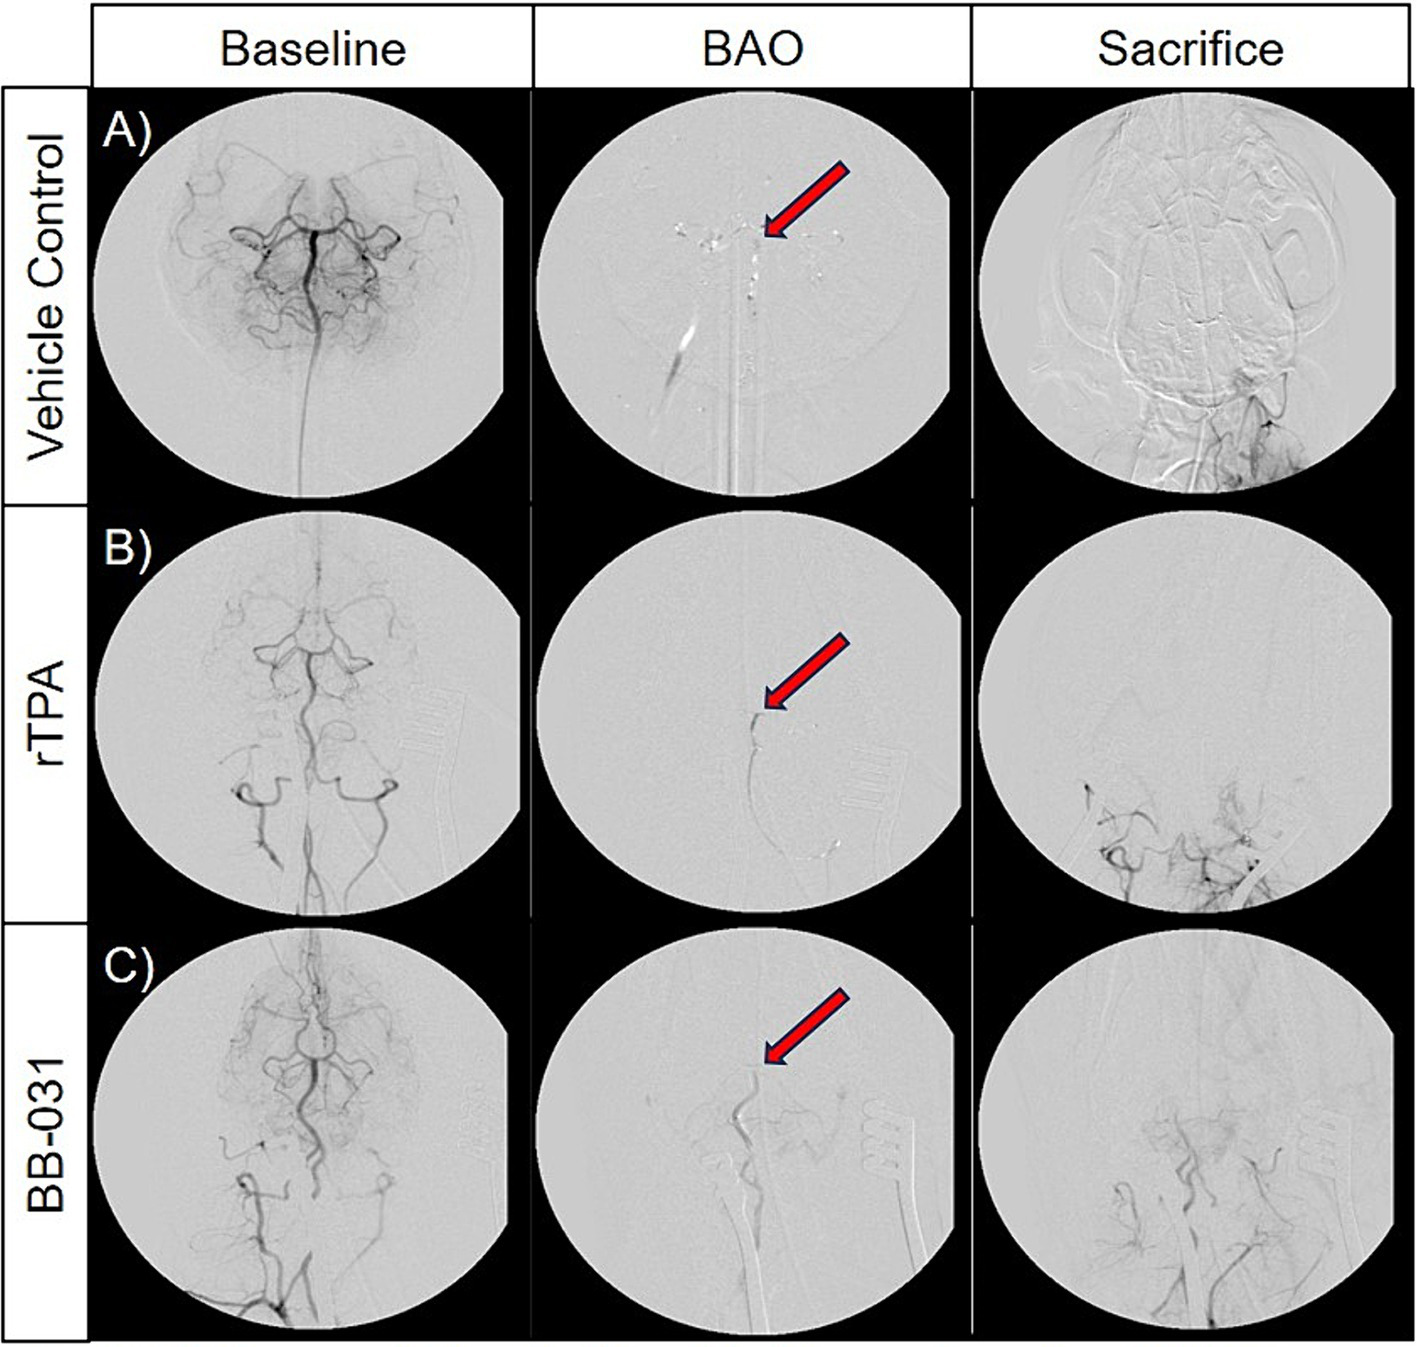

Digital subtraction angiography and recanalization

After baseline DSA was established (Figures 5A–C), consistent and sustained BAO was sustained in all 24 hounds after clot placement with no evidence of microembolism through time of sacrifice(Figures 5D–F). We found no evidence of spontaneous recanalization or intracranial perforation through serial digital subtraction angiograms during the access procedures or before/after transport for MR imaging. Although none of the vehicle treated canines resulted in TICI scoring improvement after baseline, one canine treated with 0.9 mg/kg rtPA did achieve a TICI score of 1 immediately before sacrifice (Figures G–I). BB-031 administration resulted in ≥TICI 2A in 11% and ≥ TICI 1 in 55.5% of canines compared to rtPA (p = 0.042). Perfusion was also significantly increased compared to vehicle (TICI 0, p < 0.005).

Figure 5

Representative digital subtraction angiography (DSA) images of basilar artery occlusion (BAO) in vehicle control canines (A), 0.9 mg/kg rTPA treatment canines (B), and 0.5 mg/kg BB-031 treatment canines (C) at baseline (row 1, TICI = 3), BAO (obtained 10-min post-injury, row 2, TICI = 0), and sacrifice (obtained ~4 h after occlusion, row 3). BAO site of clot placement is indicated by the red arrow in each representative images. The BB-031 treatment (TICI = 1–2) cohort displayed greater reperfusion of posterior cerebral circulation when compared to the vehicle control (TICI = 0) and rtPA (TICI = 0–1) cohorts. TICI Grade 3 = complete perfusion, 2 = partial or complete slower filling, 1 = minimal perfusion, 0 = no perfusion of occluded vessel or vessel territory.